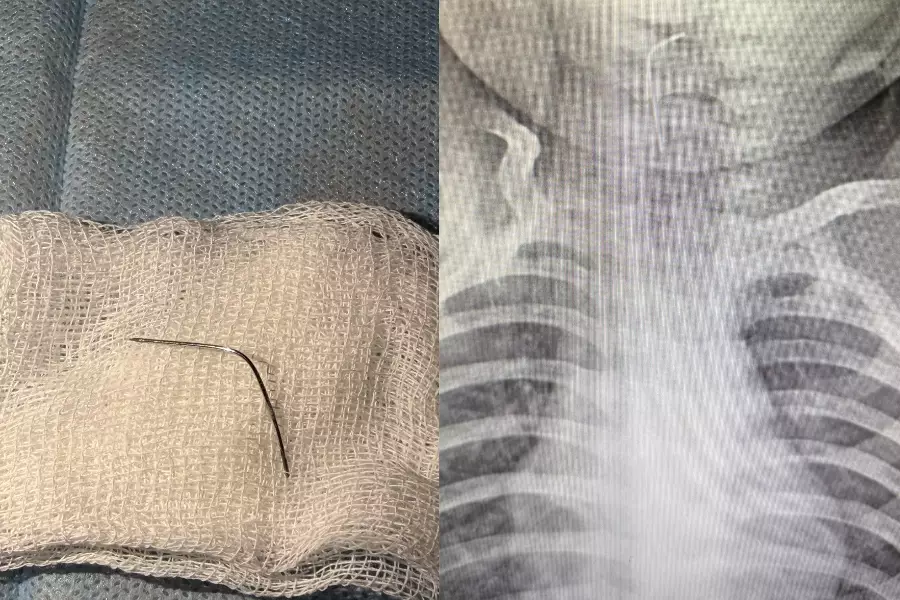

Түркістан облысында 9 айлық сәби ине жұтып қойған